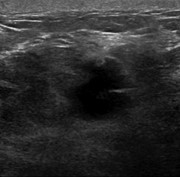

Single-incision laparoscopic management of a giant hepatic cyst

Kaitlin Willems and others

Journal of Surgical Case Reports, Volume 2015, Issue 7, July 2015, rjv073, https://doi.org/10.1093/jscr/rjv073